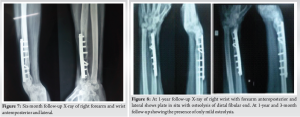

Longitudinal wide excision of right distal radius GCT was planned in view of cortical breach and soft tissue extension. Under general anesthesia, in supine position, incision was made over the dorsal aspect of wrist and forearm. The tumor capsule was identified. Under image intensifier guidance, distal radius was osteotomized. 6.5 cms proximal to distal radius articular surface to give 3 cm of tumor clearance. Using bone holder, the tumor segment with segment of 3 cm of normal bone given for clearance was lifted up (Fig. 5). Care was taken to dissect around the tumor without breaching the tumor. The ligaments of radiocarpal and radioulnar joint were divided and the tumor was delivered out/excised. Proximal fibular autograft including the fibular head was harvested from the ipsilateral right side through the posterolateral approach after isolating the common peroneal nerve. The length of the autograft harvested was around 7 cms. The distal end of this graft was stabilized to the radius with a 3.5 mm Asian dynamic compression plate and screws. Hence, the fibular head resembled and replaced the distal radius. The fibular head was stabilized with two 2 mm Kirschner wires – one fixing it to the carpus and another to the distal ulna (Fig. 6). The patient was maintained on an above elbow slab for 3 weeks and below elbow slab for further 3 weeks. The K-wires and splintage were removed after 6 weeks after which gradual mobilization of wrist and forearm was allowed. The patient was followed up at 3 months, 4 months, 6 months (Fig. 7), and 1 year (Fig. 8) and yearly once after, fibular graft was well united even at 6-month follow-up.

At 2 year and 8 months of follow-up, the patient had (Fig. 9) wrist palmar flexion of 30°, pronation of 70°, supination of 20°, dorsiflexion is NIL. The fibular graft was shorter in comparison to the length of ulna. Probably, if we had taken a longer fibular graft, range of movements may have been better as ulno-carpal impingement could have been avoided. X-ray showed that the fibular graft had well incorporated (Fig. 10).